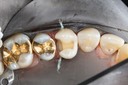

Wayne Chin #2 pre-op

Wayne Chin #2 prep

Wayne Chin #2 finish